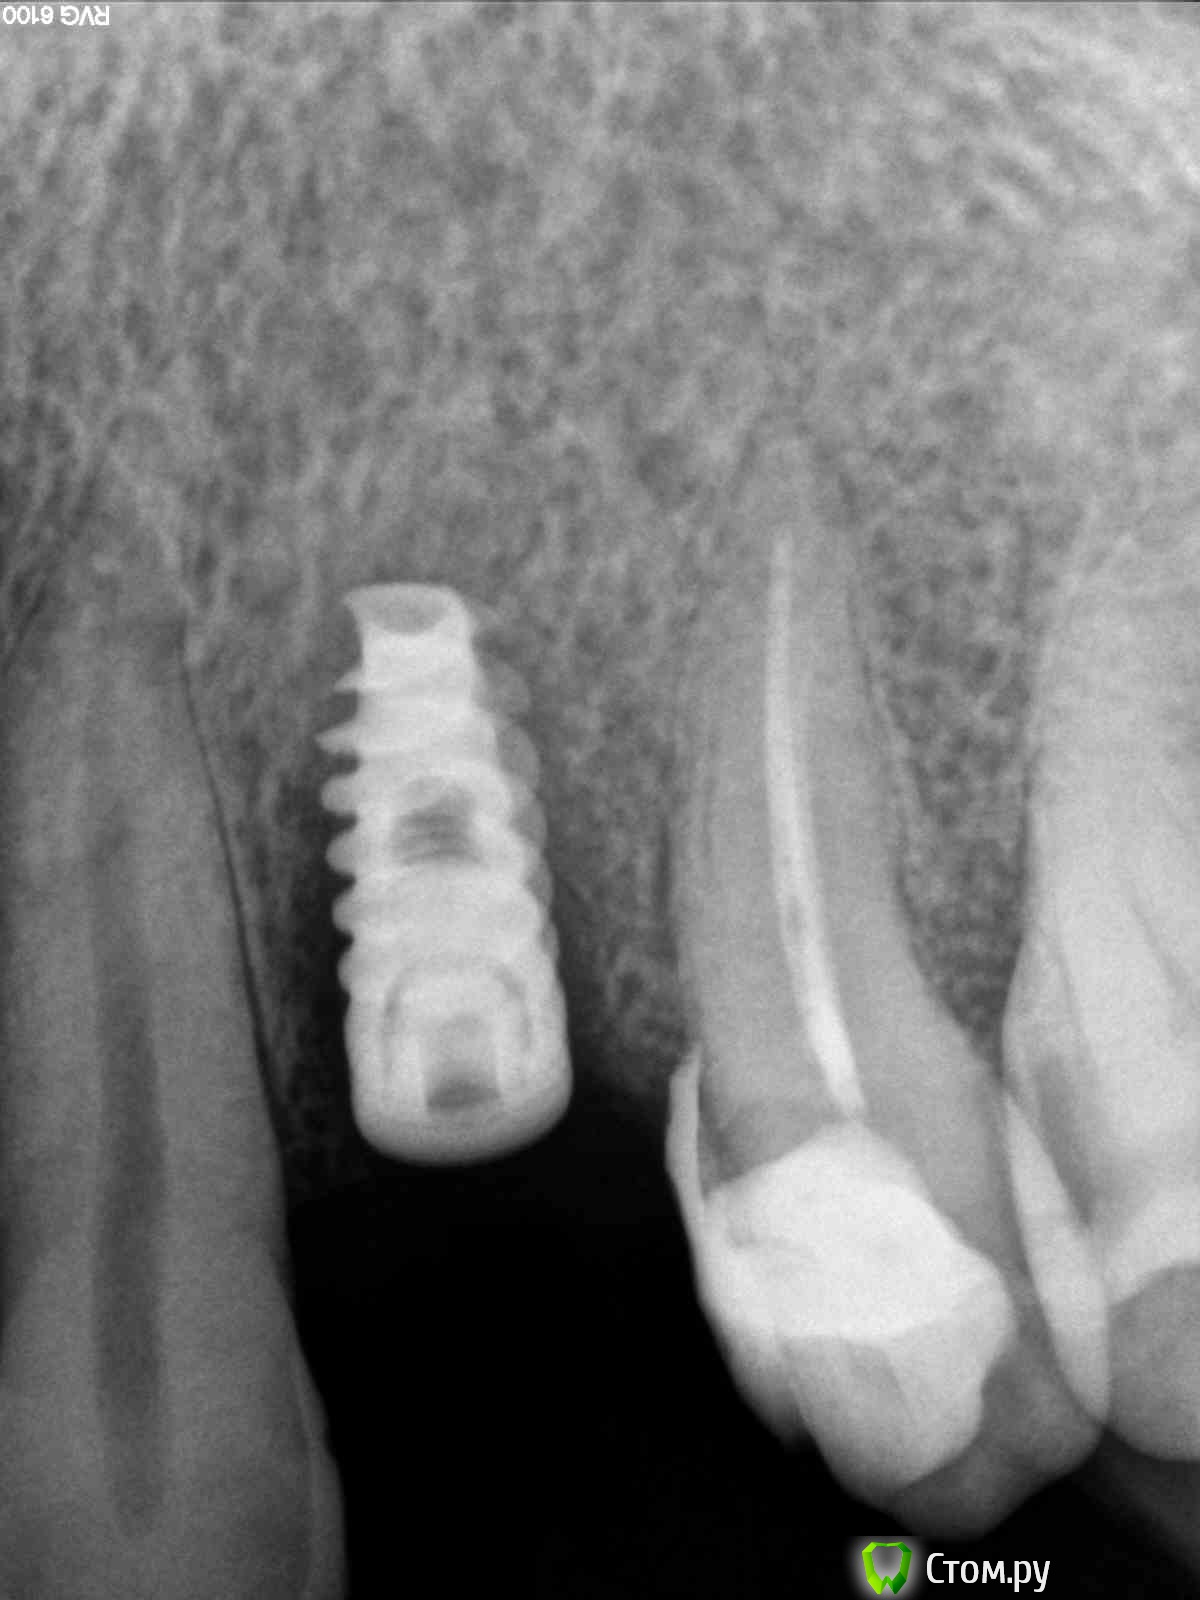

zzkz Опубликовано 24 октября, 2014 Поделиться Опубликовано 24 октября, 2014 Пациенту в области 24 зуба установил имплантат Альфа био 3,75*10. Торка хорошего не получил, поэтому даже без ФДМ.Спустя 3 месяца решил нагружать, при попытке выкрутить заглушку имплантат слегка подвижен.Роковая ошибка в том он еще не интегрировался как думаете?Как быть дальше? Выкрутить, кюретаж и подлинее? Наверно смысла ждать больше нет. Установил около 500 штук. Это первый подобный неудачный случай. Ссылка на комментарий

zzkz Опубликовано 24 октября, 2014 Автор Поделиться Опубликовано 24 октября, 2014 Ставить более широкий было бы очень близко к корням.Снимок прилагаю. Что скажете по поводу сроков? Рано все таки полез учитывая торк? Ссылка на комментарий

Фарид Расулыч Опубликовано 24 октября, 2014 Поделиться Опубликовано 24 октября, 2014 Остеоинтеграции не произошло. А почему это уже другой вопрос. Ну в данном случае можно подлиннее. Это мое мнение. Ссылка на комментарий

zzkz Опубликовано 24 октября, 2014 Автор Поделиться Опубликовано 24 октября, 2014 Остеоинтеграции не произошло. А почему это уже другой вопрос. Ну в данном случае можно подлиннее. Это мое мнение.Смотрю на сегодняшний снимок и думаю почему подлиннее не поставил) spi же? Он самый 1 Ссылка на комментарий

Тимур86 Опубликовано 24 октября, 2014 Поделиться Опубликовано 24 октября, 2014 Так там кость ушла,чего ждать? Ссылка на комментарий